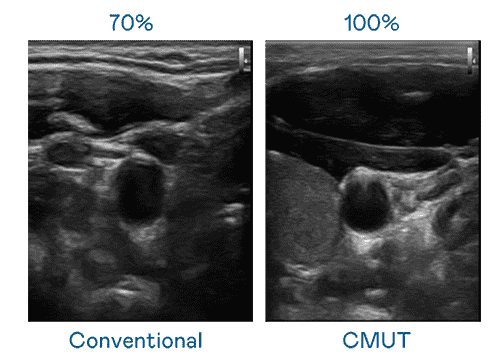

CMUT 技术是一种用电容式微机电元件来产生超音波讯号的技术。。。与传统 PZT 压电式技术相比,,,,CMUT 频宽增加 30%,,,更宽频的超音波讯号让影像解析度大幅提升,,是实现高影像品质医疗超音波扫描、、、促进精准医疗发展的关键技术。。。。

大频宽带来超清晰影像

超音波影像的解析度高低,,,首先取决于探头能发出的讯号频宽。。。森林舞会 CMUT 可提供高清晰的超音波讯号,,提供高频宽、、高灵敏度、、、影像纹理细节更高的超音波影像,,,协助医护人员缩短影像判读时间及利用精准的医疗影像进行诊断。。。。